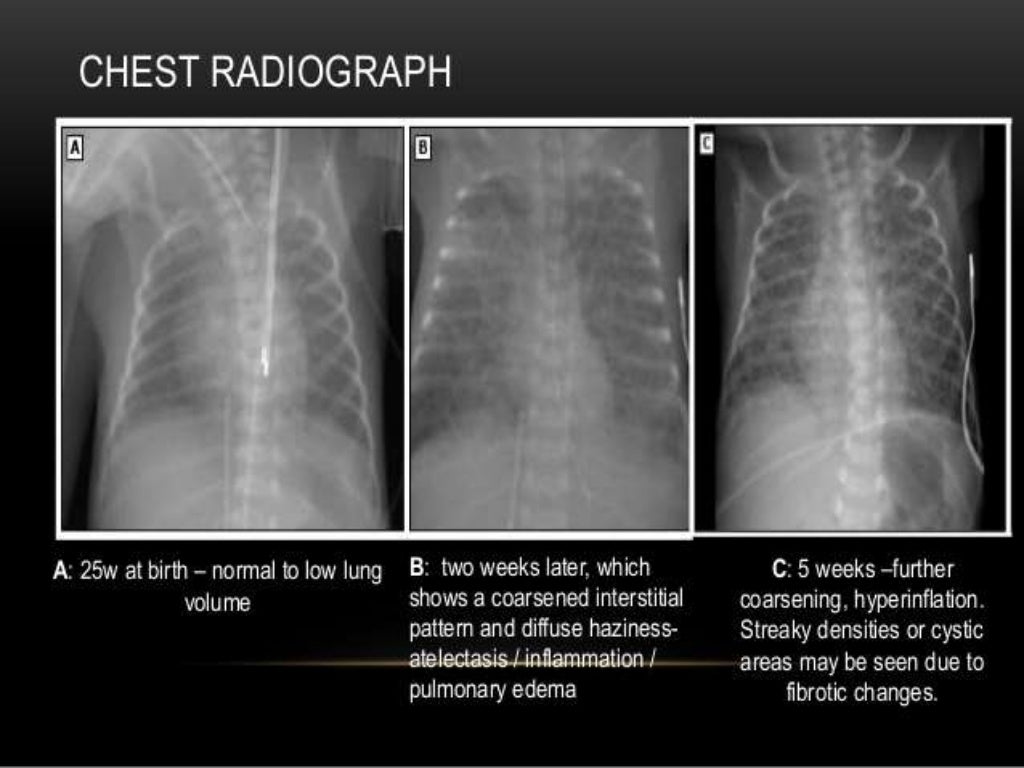

Bronchopulmonary dysplasia

PPT Bronchopulmonary Dysplasia PowerPoint Presentation ID2184240 What Is A Borderline Chest X Ray Doctors typically use this procedure to help diagnose breathing difficulties, a bad or persistent cough,. Mild cardiomegaly is when your heart is just a little bigger than it should be (slightly larger than your fist). It depends on question asked by clinician for examination. On the top portion of the chest are the neck and the collar bones. An enlarged. What Is A Borderline Chest X Ray.

PPT Bronchopulmonary Dysplasia PowerPoint Presentation ID791706 What Is A Borderline Chest X Ray It depends on question asked by clinician for examination. It’s often one of the first tests they use to diagnose broken bones or lung. On the top portion of the chest are the neck and the collar bones. Mild cardiomegaly is when your heart is just a little bigger than it should be (slightly larger than your fist). An enlarged. What Is A Borderline Chest X Ray.

Bronchopulmonary dysplasia The Clinical Advisor What Is A Borderline Chest X Ray On the top portion of the chest are the neck and the collar bones. It depends on question asked by clinician for examination. However, it may identify contributing lung. It’s often one of the first tests they use to diagnose broken bones or lung. Mild cardiomegaly is when your heart is just a little bigger than it should be (slightly. What Is A Borderline Chest X Ray.

Old "Classic" BPD xray showing areas of atelectasis, fibrosis and What Is A Borderline Chest X Ray However, it may identify contributing lung. An enlarged heart (cardiomegaly) isn't a disease, but rather a sign of another condition. It’s often one of the first tests they use to diagnose broken bones or lung. On the top portion of the chest are the neck and the collar bones. Doctors typically use this procedure to help diagnose breathing difficulties, a. What Is A Borderline Chest X Ray.